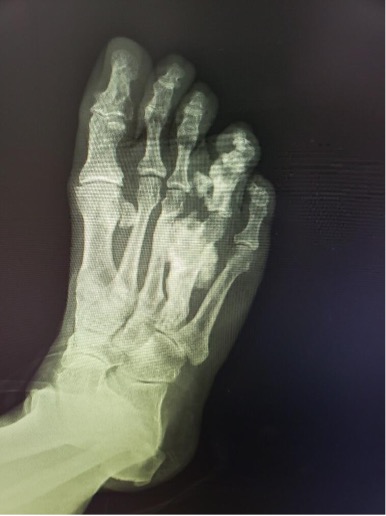

On plain films, one could note radiodensity at the right fourth metatarsal shaft and right fourth proximal and middle phalanges with significant hypertrophic osseous formation of the right fourth metatarsal shaft and right fourth proximal phalanx. The fourth digit appeared pedunculated from the medial aspect of the base of the proximal phalanx with possible synostosis to the right third metatarsal shaft.

Magnetic resonance imaging (MRI) showed abnormal cortical thickening, expansion, and irregularity of the fourth ray, including involvement of the metatarsal and all the phalanges. Based on radiography there was involvement of the calcaneus (seen on lateral view). Plain film radiography revealed involvement of the calcaneus, seen on the lateral view. There was a soft tissue mass noted at the distal aspect of the fourth ray. There was ossification in the plantar soft tissues contiguous with the fourth ray hyperostosis.

These findings were felt to be most consistent with a dysplastic bone disease; likely melorheostosis. The treatment team then decided to pursue surgical intervention.